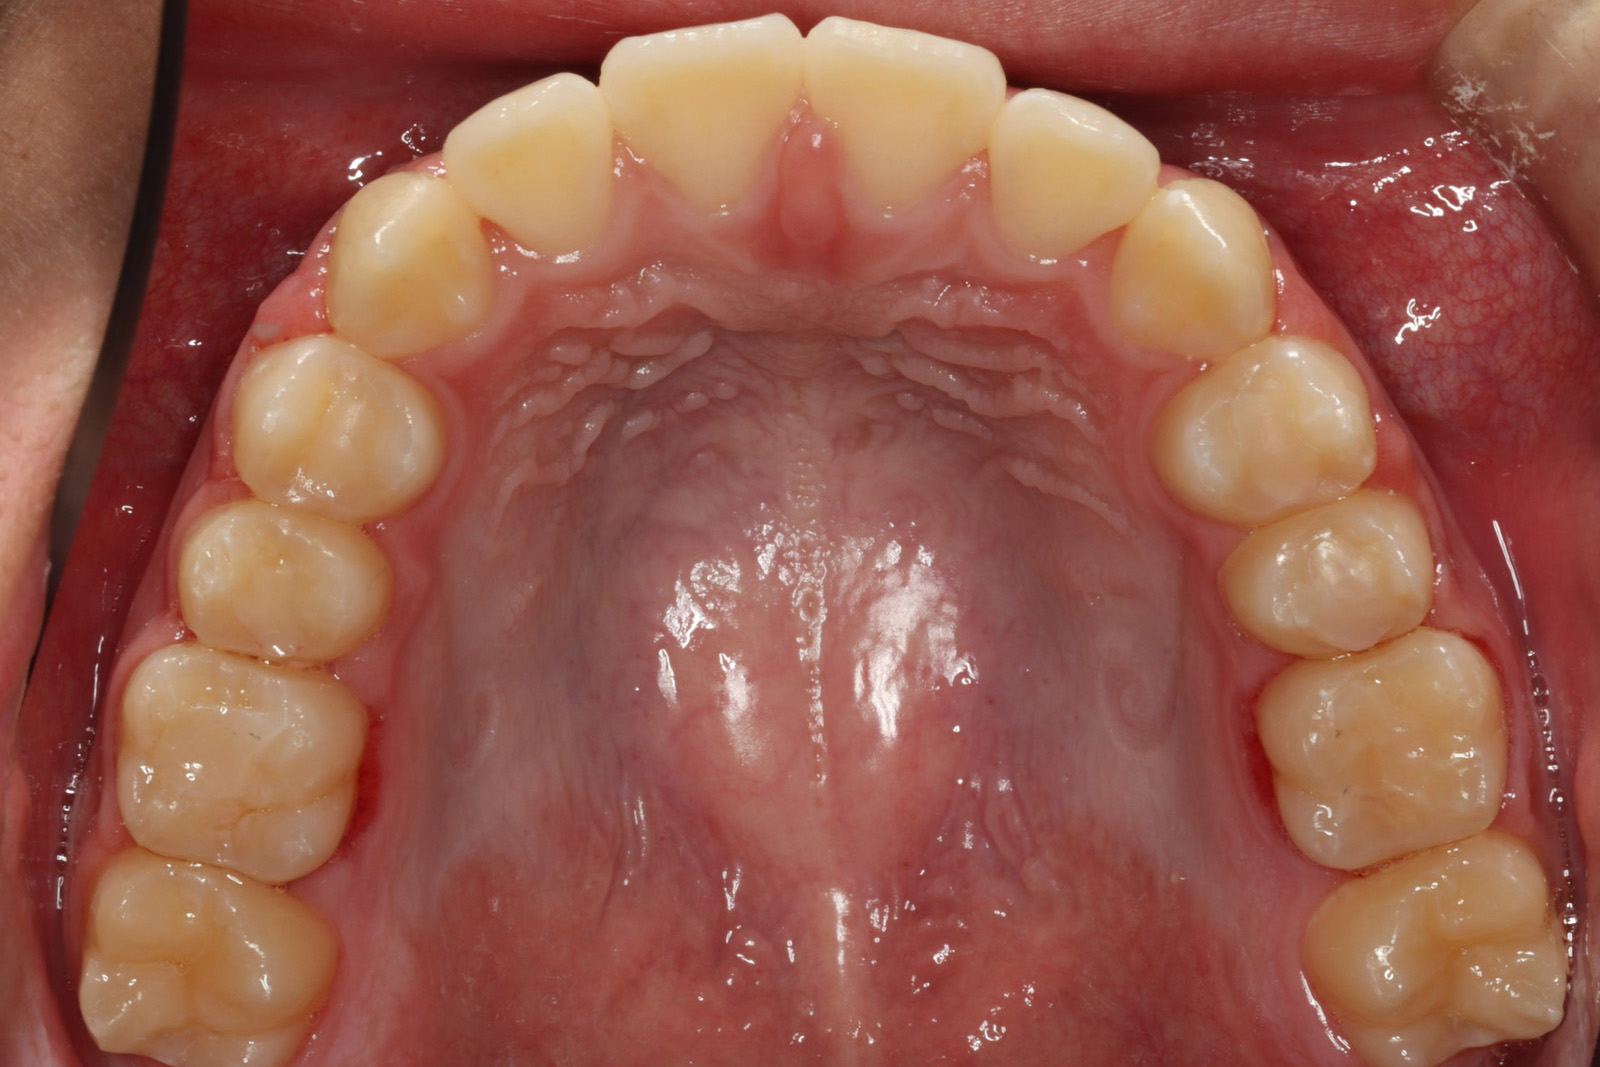

問診を行い、お口の悩みや希望を確認します。レントゲン撮影や口腔内写真の撮影など、必要に応じた精密検査を行います。

検査結果に基づき、現在の状態と治療計画(期間や費用含む)についてご説明します。